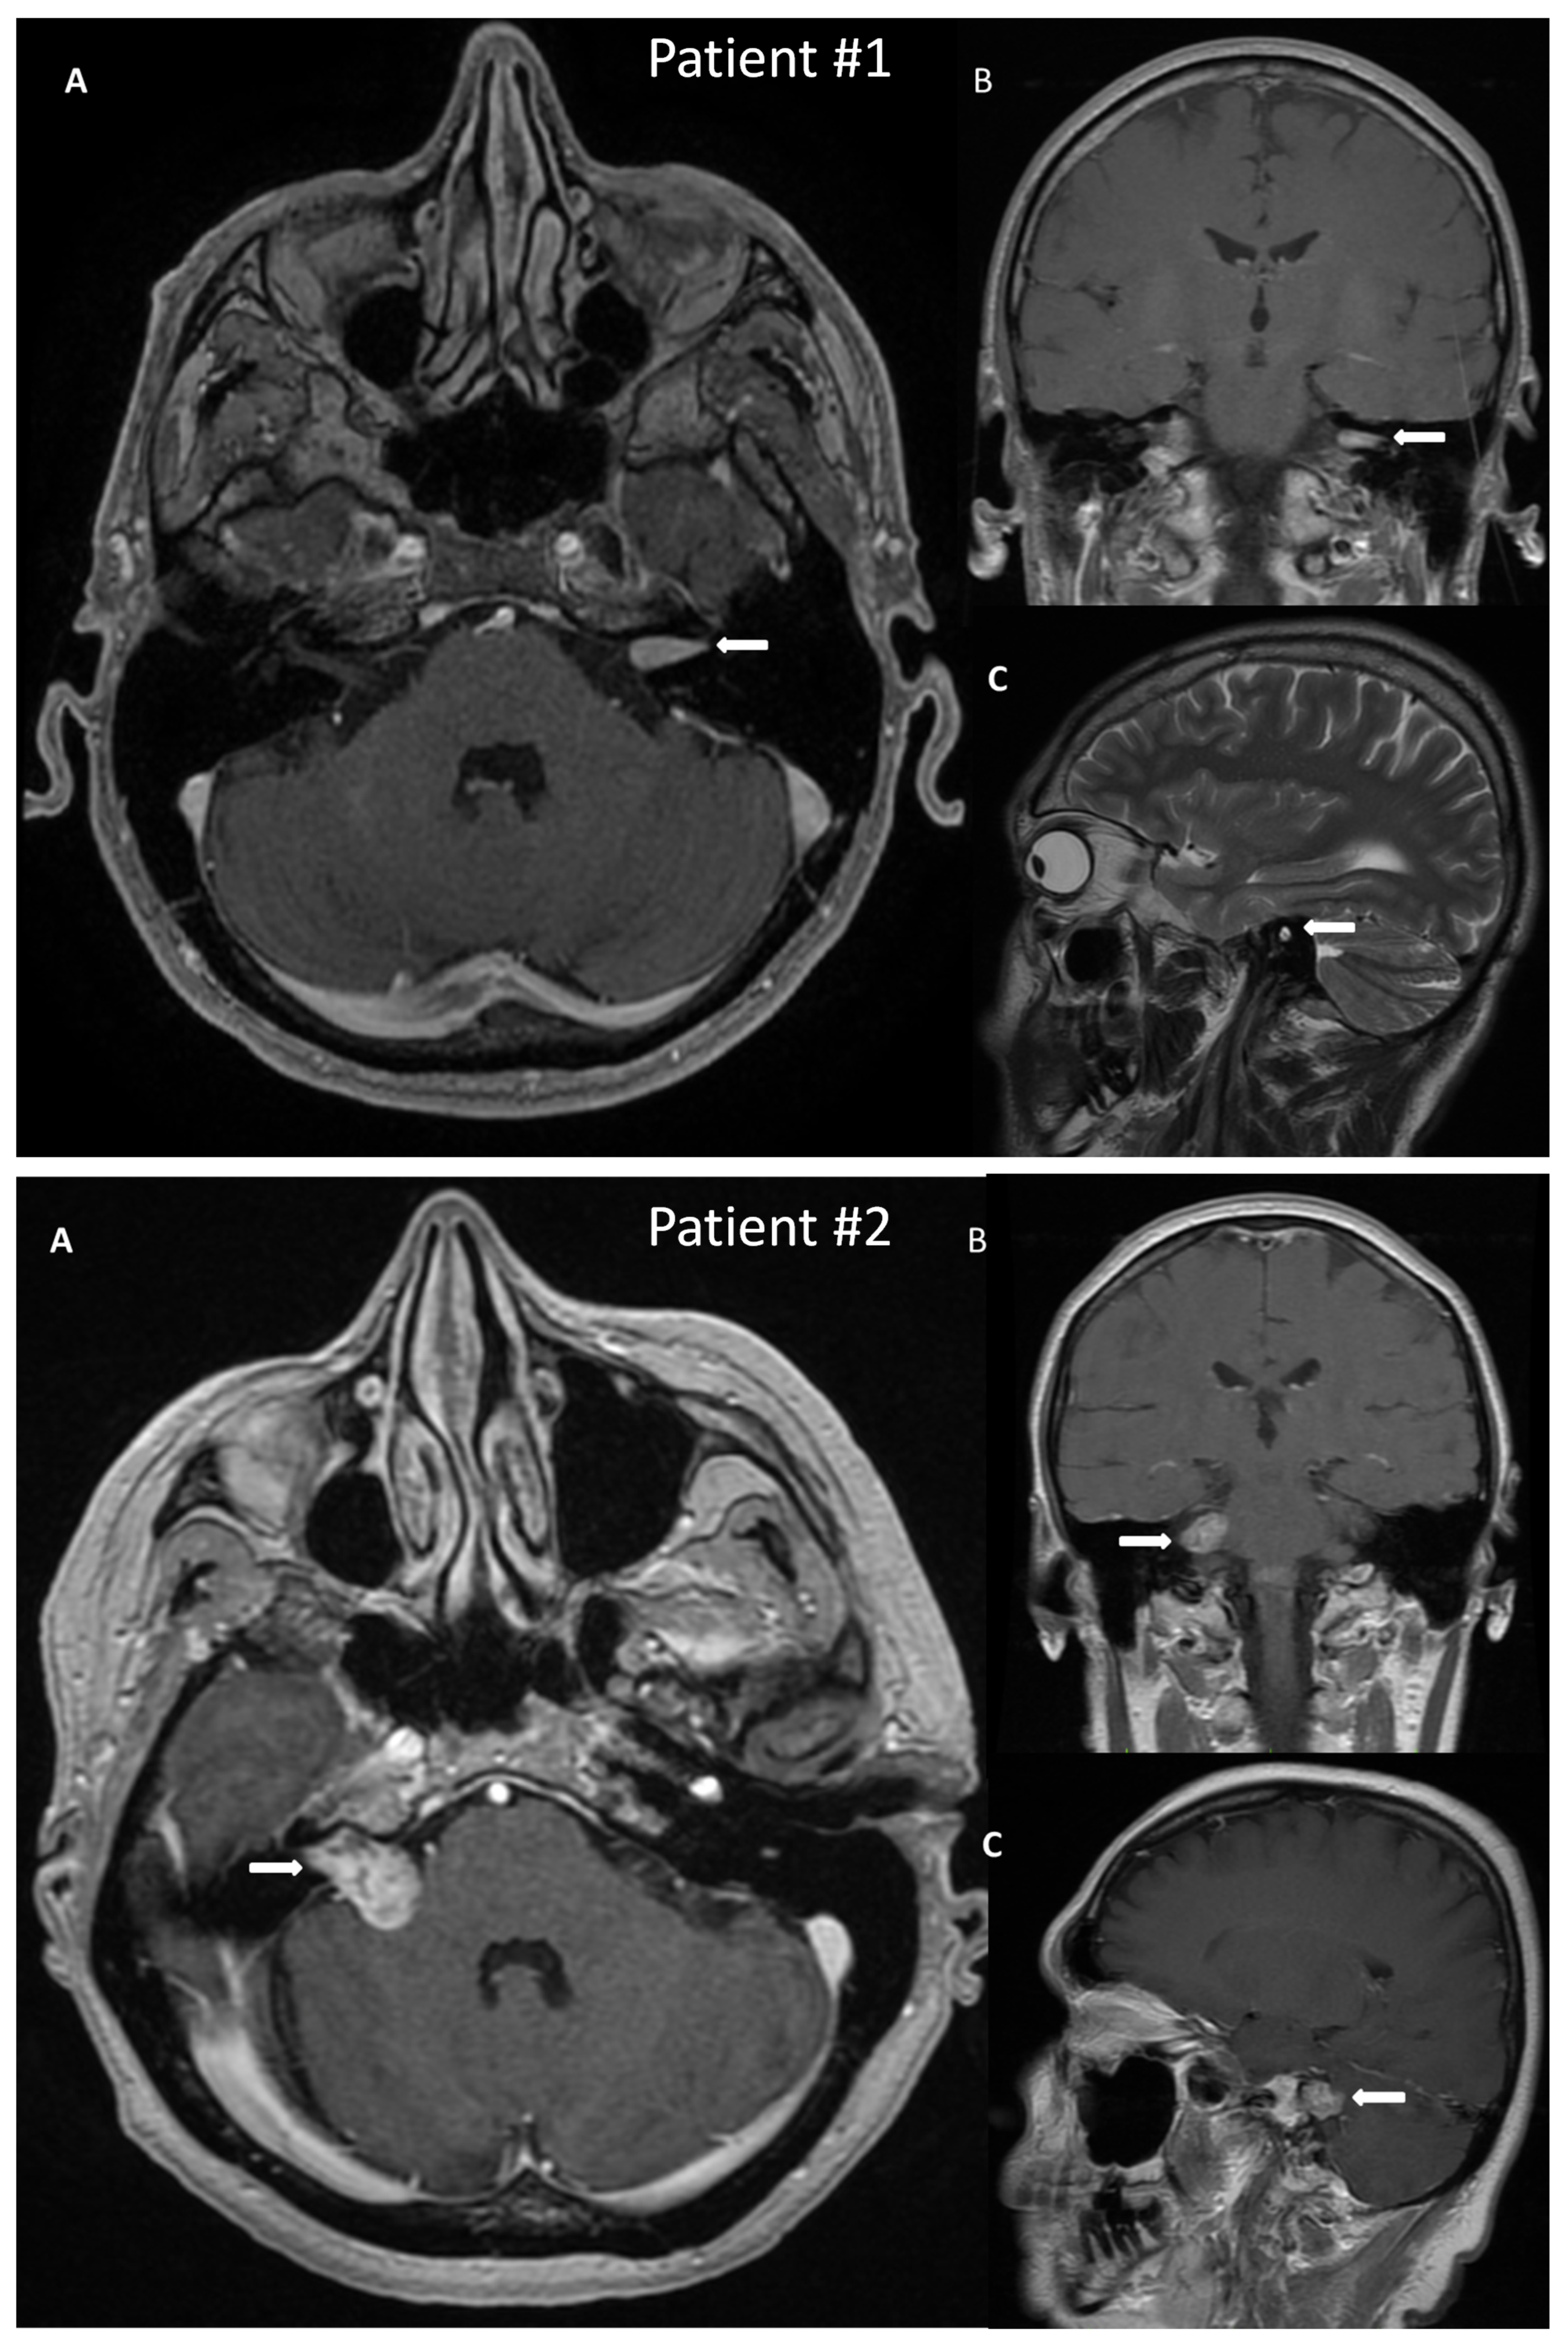

3.1.1. Case Example—Patient #1